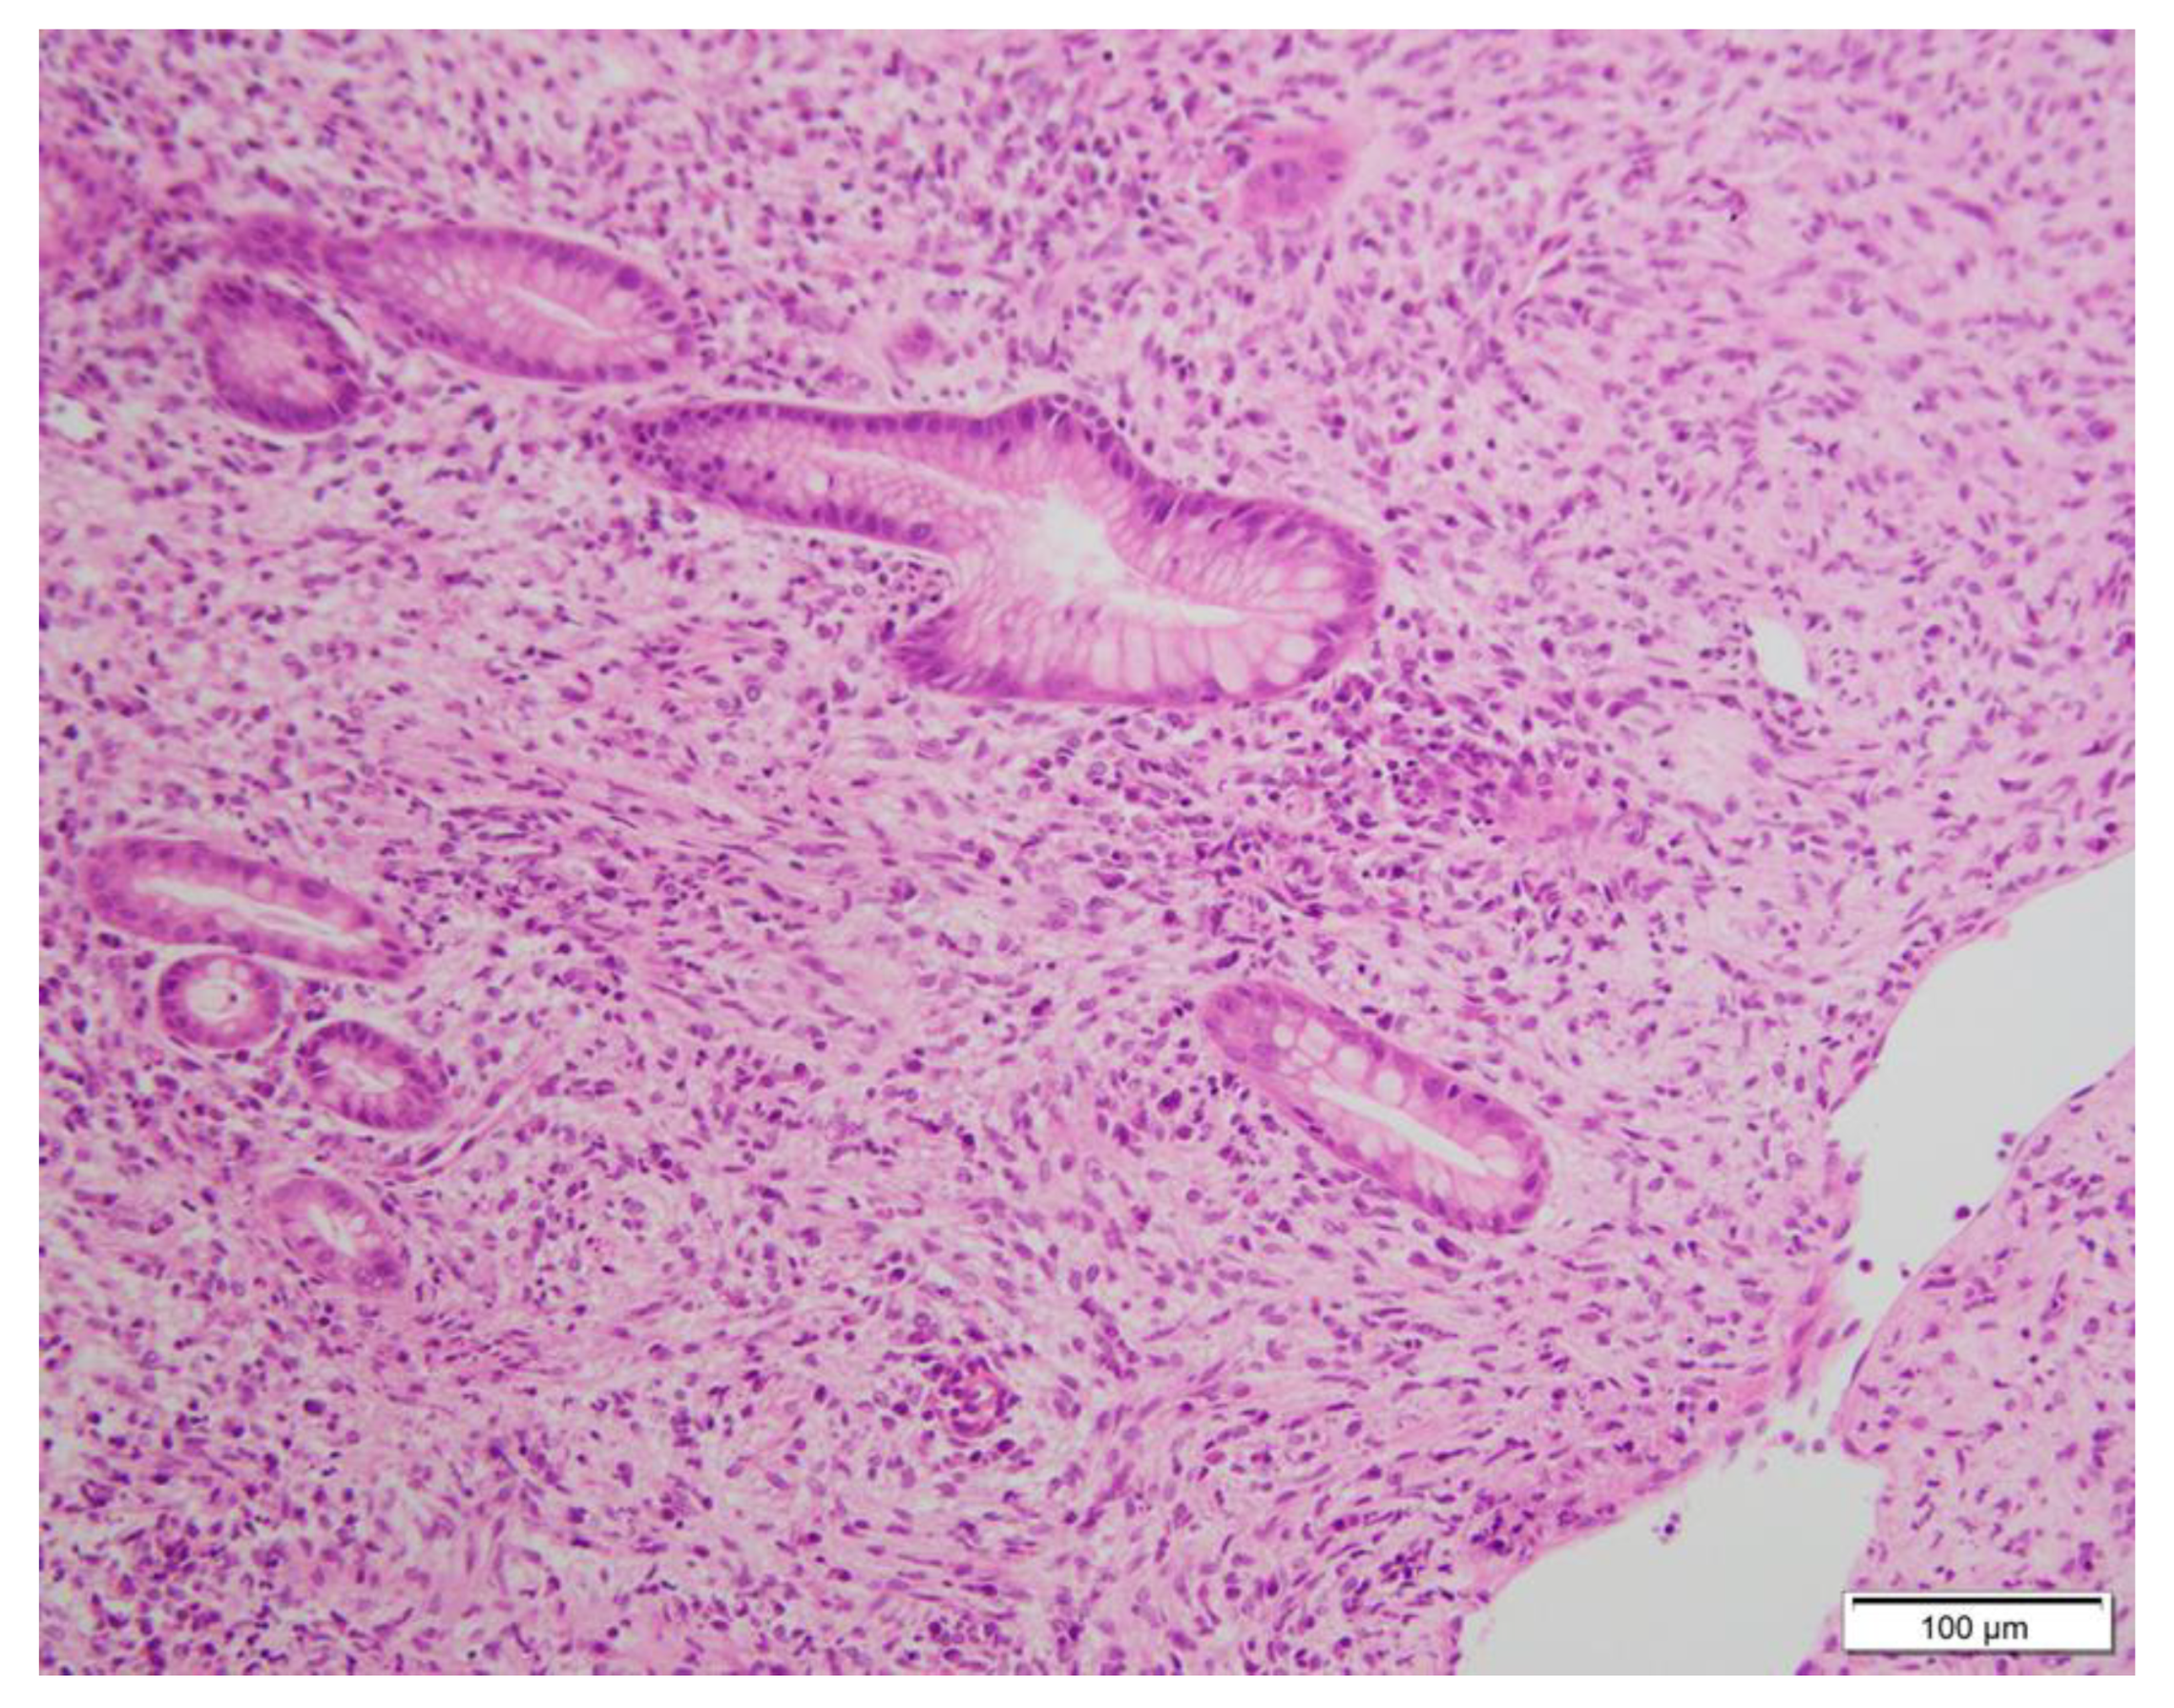

GISTs are commonly encountered tumours in routine practice. In the main tumour, the morphology of spindle, epithelioid, or mixed cells are well recognised, along with mutations of c-kit. In this article, the results of the H&E staining for histology by GIST microscopy reveal that it is mainly composed of spindle and epithelioid-like cells (Figure 3). CD117 is the most characteristic diagnostic marker of GIST. Its combination with DOG1 and CD34 testing has always been used as the main indicator of GIST diagnosis [10,11]. Antonescu CR et al. showed that GISTs usually exhibit monotonous morphology characterized by uniform cells with minimal cytologic atypia, rare mitoses, and immunoreactivity for CD117, which is encoded by the KIT gene [11]. Approximately 95% of classic GISTs typically express CD117 and CD34 in about 60–70% of the lesions [12]. In addition, Novelli M et.al showed that DOG1 and CD117 are the most sensitive and specific antibodies used in GIST diagnosis [13]. The expression of Ki-67 has significant value in predicting the risk grade and prognosis of GISTs. GISTs present a risk of recurrence and metastasis, so patients may need a close follow-up [14].

Figure 3.

Gastroscopy biopsy tissue H&E stain can be seen from scattering cells. (H&E stain, ×200). According to the form of tumour cells, GIST is divided into three major subtypes: spindle cell, epithelial sample, and mixed type. The rare types include de-differentiated types. Spindle cell accounts for 50% to 70%. It is mainly composed of scattering cells with relatively consistent morphology. The density, heterogeneity, and nuclear split elements of tumour cells vary for each case. Some GIST cases can be seen on the nuclear end. Slipper cells are mostly arranged or intertwined, and sometimes there are a variety of arrangements, such as organs, fake chrysanthemum-shaped groups, or fences [15].